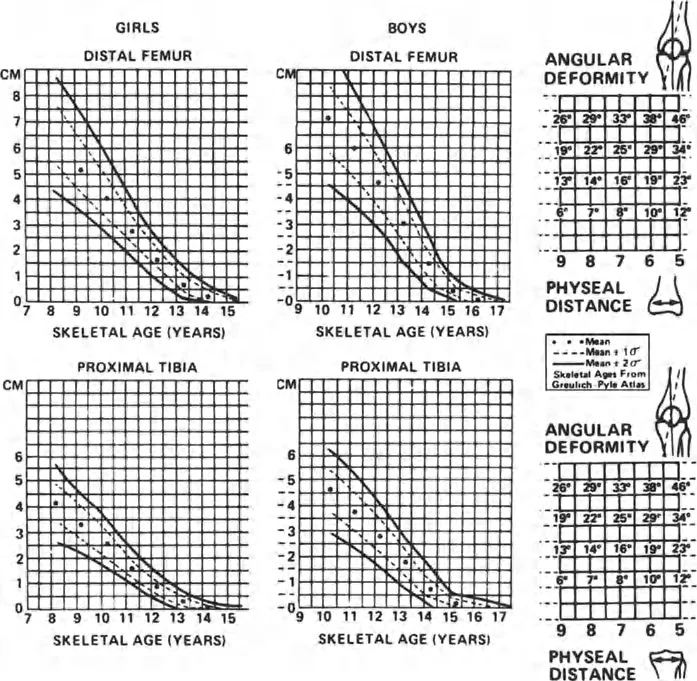

زاوية الكاحل الظهرية الظنبوبية (ADTA)

تُستخدم زاوية الكاحل الظهرية الظنبوبية (ADTA) كمعيار تشخيصي مهم لتقييم مدى تقوس الكاحل. وهي تقيس الزاوية بين محور عظم الظنبوب ومستوى عظم الكاحل. في الوضع الطبيعي، تسمح هذه الزاوية بحركة كافية لثني القدم للأعلى. أي انحراف عن هذه الزاوية الطبيعية يمكن أن يشير إلى وجود تقوس أو تشوه.

- قياس نطاق الحركة (Range of Motion): تقييم قدرة الكاحل والقدم على الثني للأعلى والأسفل، والقلب للداخل والخارج. يتم قياس زاوية الكاحل الظهرية الظنبوبية (ADTA) لتحديد درجة تقوس الكاحل.

- الأشعة السينية (X-rays):

- تعتبر الأشعة السينية ضرورية لتقييم العظام، وتحديد وجود أي كسور، سوء التئام، نتوءات عظمية، أو تشوهات هيكلية مثل تقوس الظنبوب البعيد أو عظم الكاحل المسطح.

- تساعد في قياس الزوايا المختلفة، مثل ADTA، لتحديد درجة تقوس الكاحل.